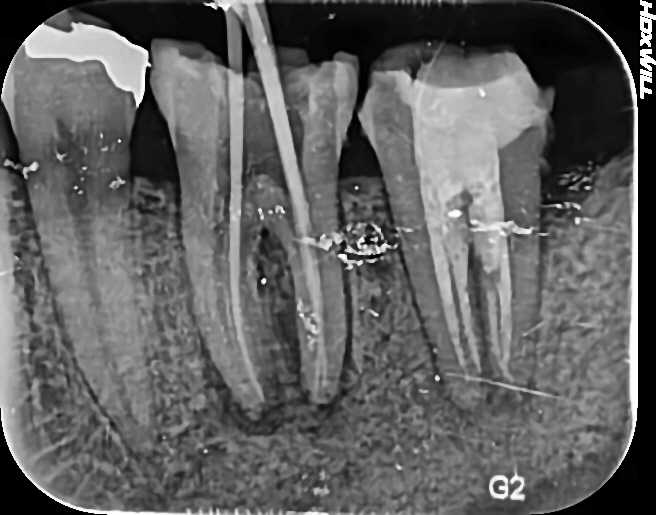

[수서 신혼희망타운 치과] 치근단 염증 신경치료

안녕하세요 수서역치과 수서신혼희망타운 치과 치과 보철과 전문의 이재현입니다 예전에 치근단 염증으로 ...